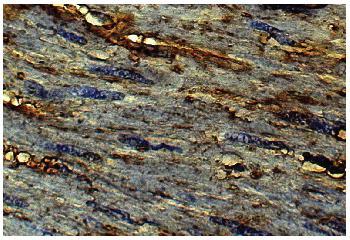

Goat Anti-Type VI Collagen

Figure 1: Human kidney cancer tissue was stained with Goat Anti-Type VI Collagen followed by Swine Anti-Goat IgG(H+L), Human/Rat/Mouse SP ads-Biotin and Streptavidin-HRP .